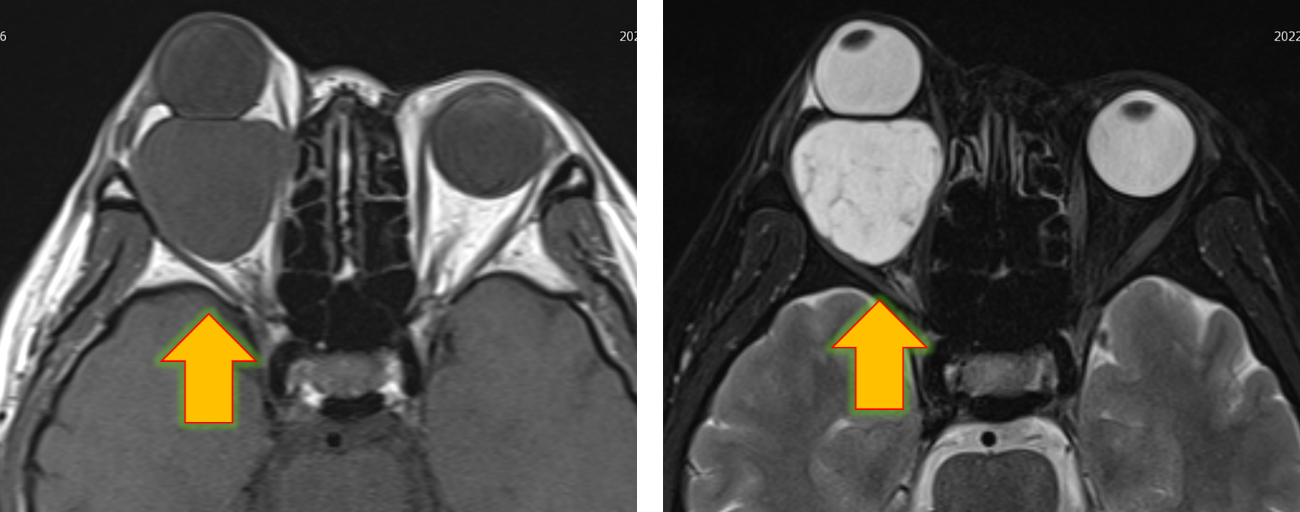

術前のMRI

眼球より後方に腫瘍があり、眼球を押し上げていることが分かります。

術後MRI

腫瘍はきれいに摘出され、眼球は凹んでいます。